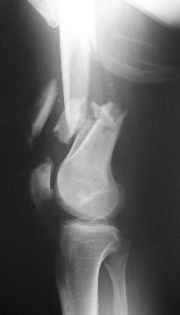

Open supracondylar femur fx

What would be your method of choice to fix this Gr IIIa open high energy supracondylar femur fx, neuro vasculary intact.

30 YO male MBA hemodynamically stable, no chest injuries. Right temporal bone fx, no IC bleeding on the head CT. Images attached. Best Regards, Zsolt Balogh, MD Trauma Surgeon Szeged, Hungary